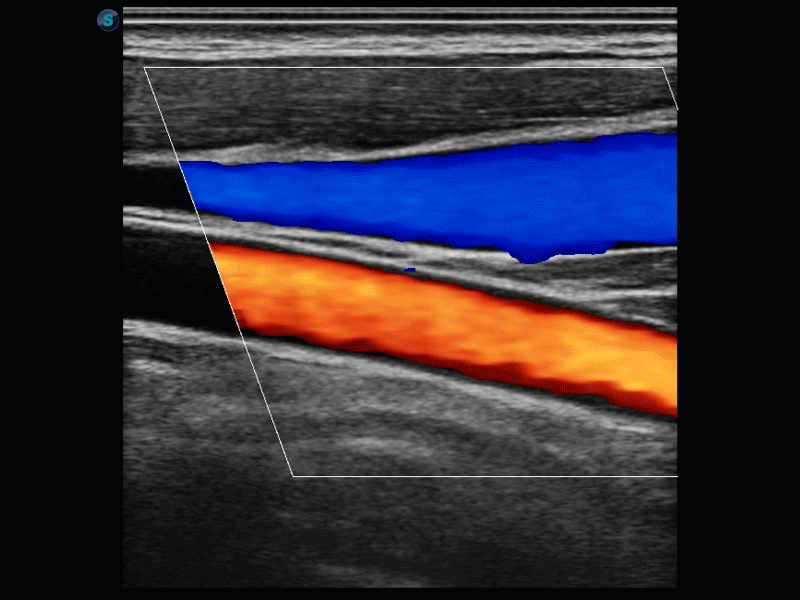

实时宽景成像技术

通过彩色血流和实时宽景相结合,可观察到完整的动静脉血流,方便医生检查。实时扫查过程中,如有任何操作失误也可以很容易地进行回扫擦除,而不会中断扫查。